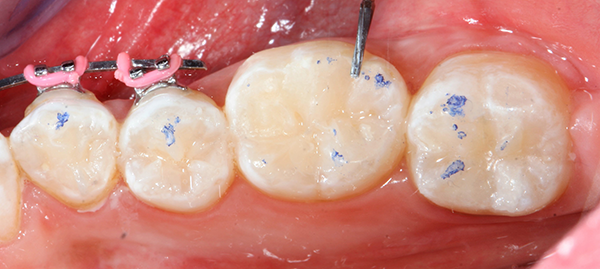

Occlusion was checked with articulating paper (AccuFilm®, Parkell) (Fig. 7) and adjusted as needed with a finishing bur (Fig. 8).

Fig. 7 Fig. 8

As one can observe from the pictures, when anatomy is closely followed in the reconstruction of the missing tooth structure, necessary occlusal adjustment is very minimal.